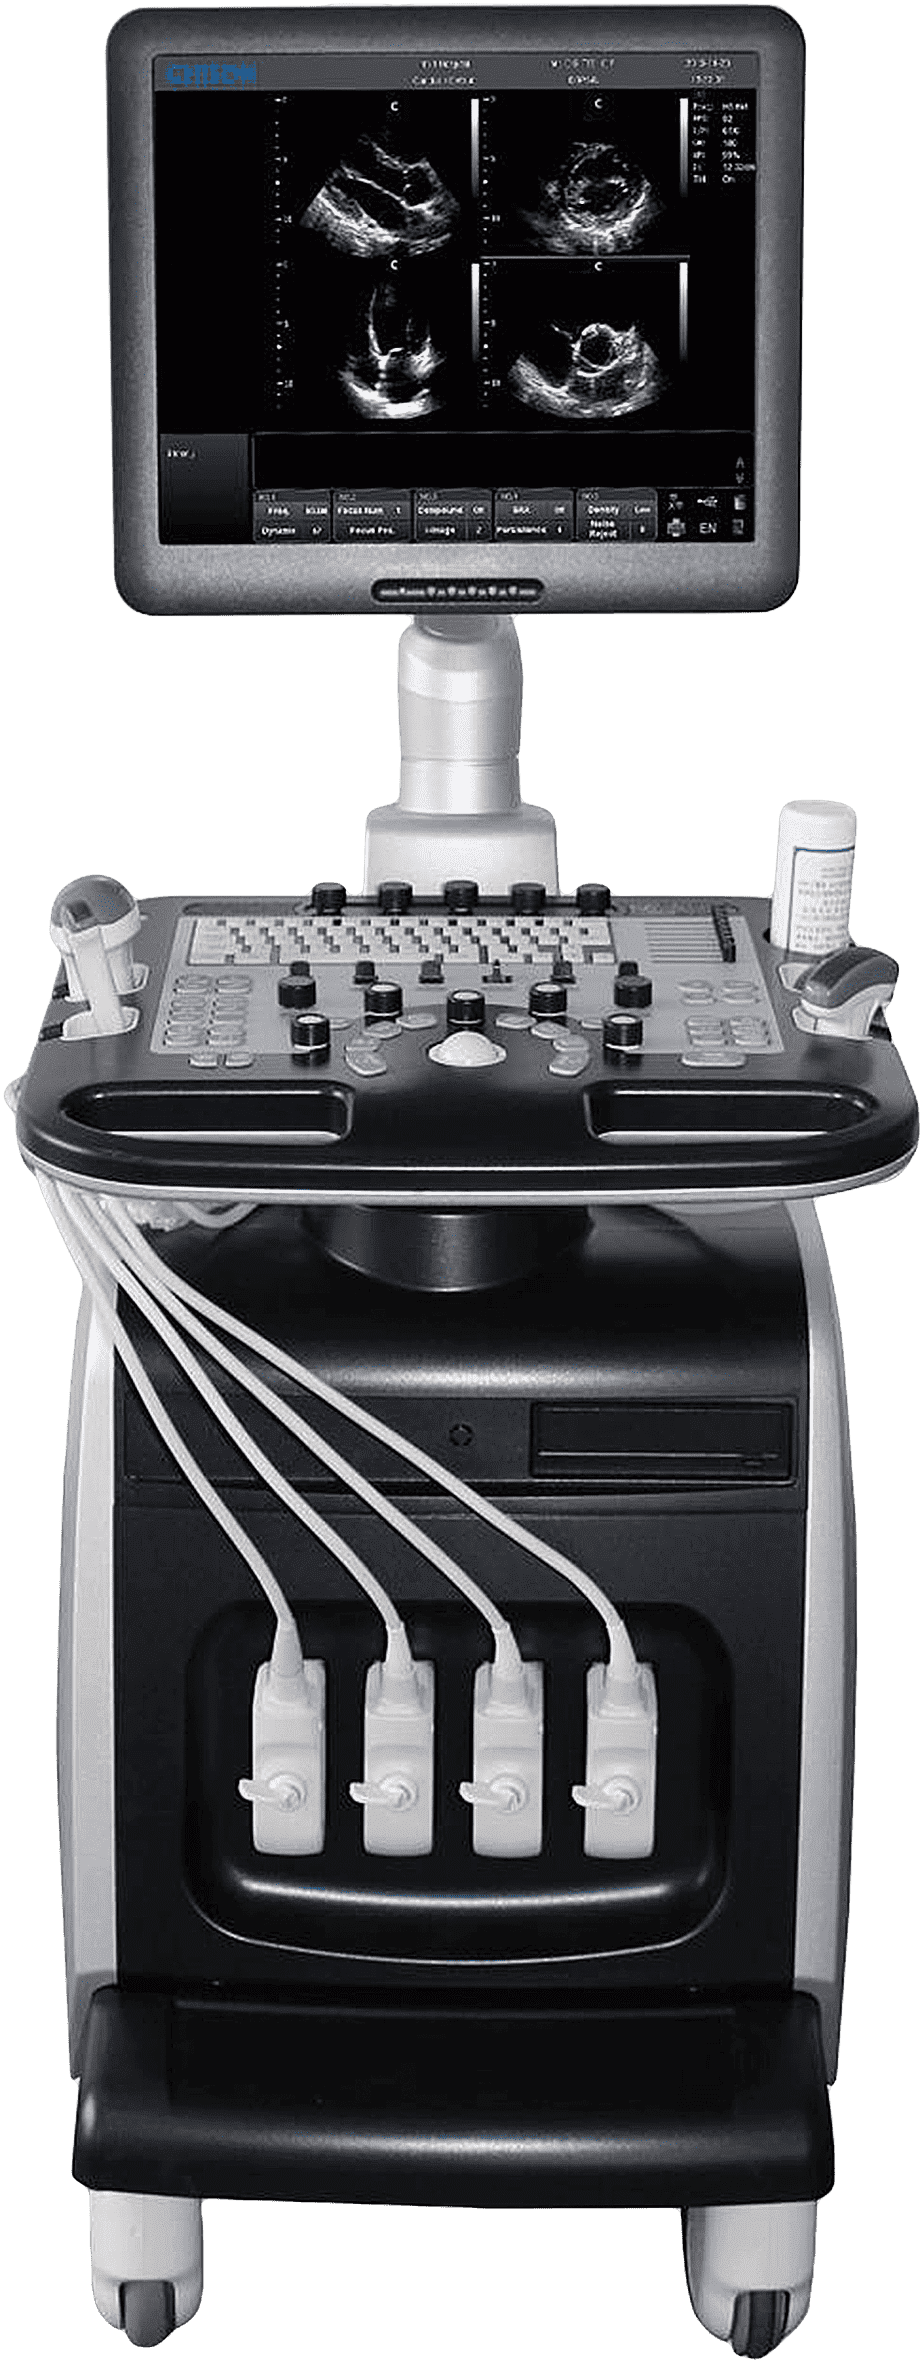

Стационарная ультразвуковая система Chison i8 – современный усовершенствованный и высокотехнологичный аппарат, преимуществом которого являются: компактность, мобильность, широкий диапазон областей применения, возможность работы с качественными контрастными изображениями без шумов и искажений.

Инновационные технологии. УЗИ-сканер Chison i8 уникален тем, что работает на основе самых новейших передовых технологий, повышавших качество визуализации и упрощающих процесс работы: технология 4D, Compound, i-Image, SRA, THI, Супер-игла.

Продуманность и удобство. Миниатюрный дизайн ультразвукового аппарата позволяет ему размещаться практически в любых помещениях. Пользователь сможет без труда увидеть все детали изображения на большом ЖК-мониторе с диагональю 19 дюймов.

Высокое качество изображения доступно за счет применения инновационных технологий и широкого спектра режимов сканирования, среди которых есть: Power Doppler/Directional PD, B, Duplex, Quadplex, 2B, B/M, B/BC, 4B, CFM, PW, Instant Triplex, Trapezoidal, Chroma B&M&PW.

Технические характеристики:

- Дисплей 19 дюймов;

- Порты для 4 датчиков;

- Дисковод DVD-R/W;

- Жесткий диск 320G.